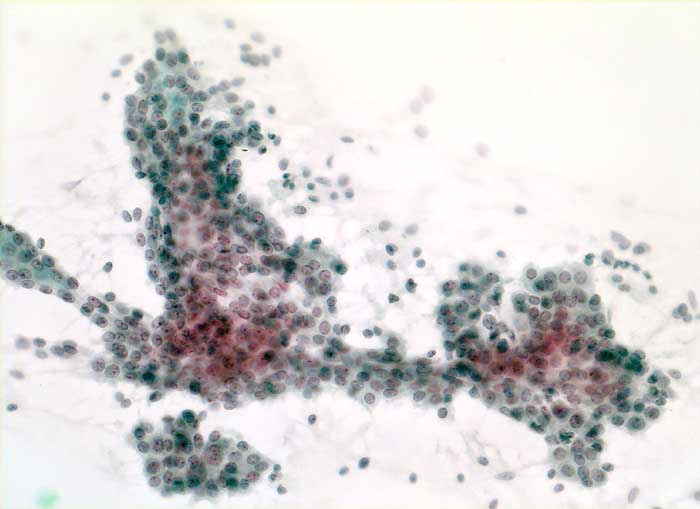

PathoPic ID 5669 - Fibroadenom

Fibroadenom

benigner Tumor

Mamma

Feinnadelpunktion Mamma: Grösserer unregelmässig verzweigter Verband unverdächtiger Mammaepithelien und massenhaft bipolare nackte Kerne (

Myoepithelien).

Zytologische Diagnose: Befund gut vereinbar mit Fibroadenom

Zytologie

200

18